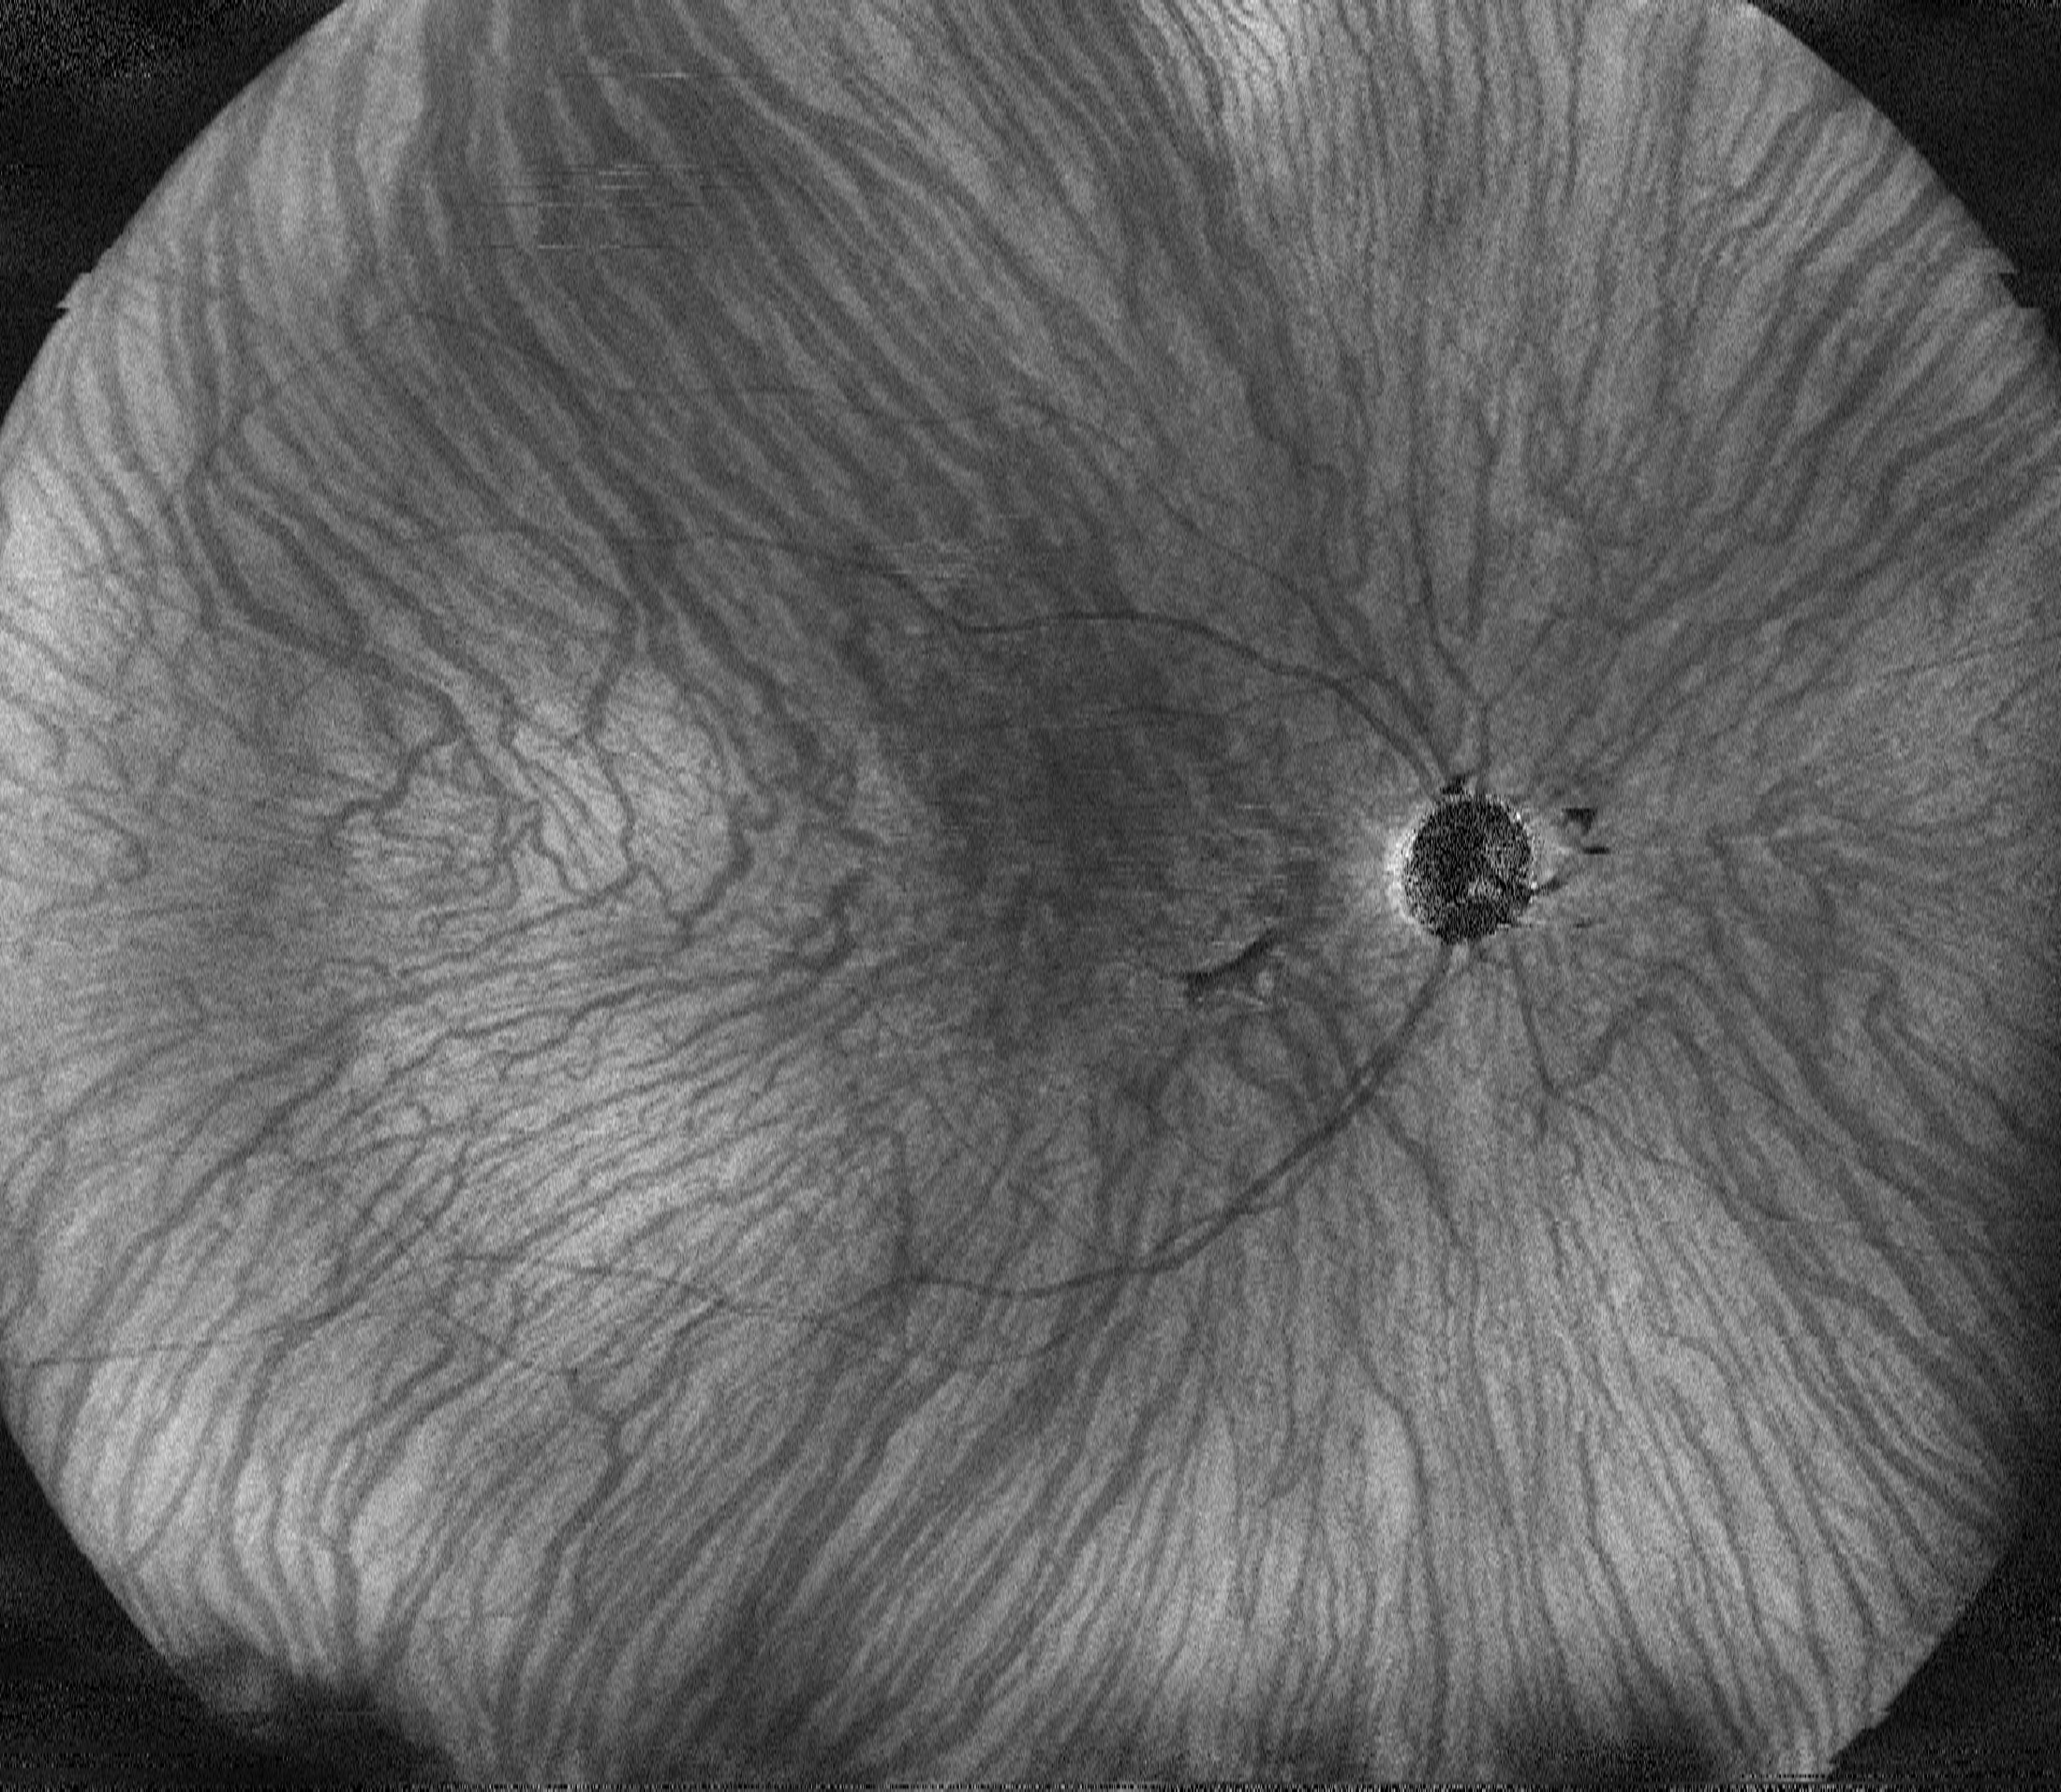

Малюнок 3. Нова сегментація шарів за допомогою технології штучного інтелекту Deep Learning. Відображення межі хоріоідея/склера. Покрашена візуалізація enface зображення шару хоріодіеї.